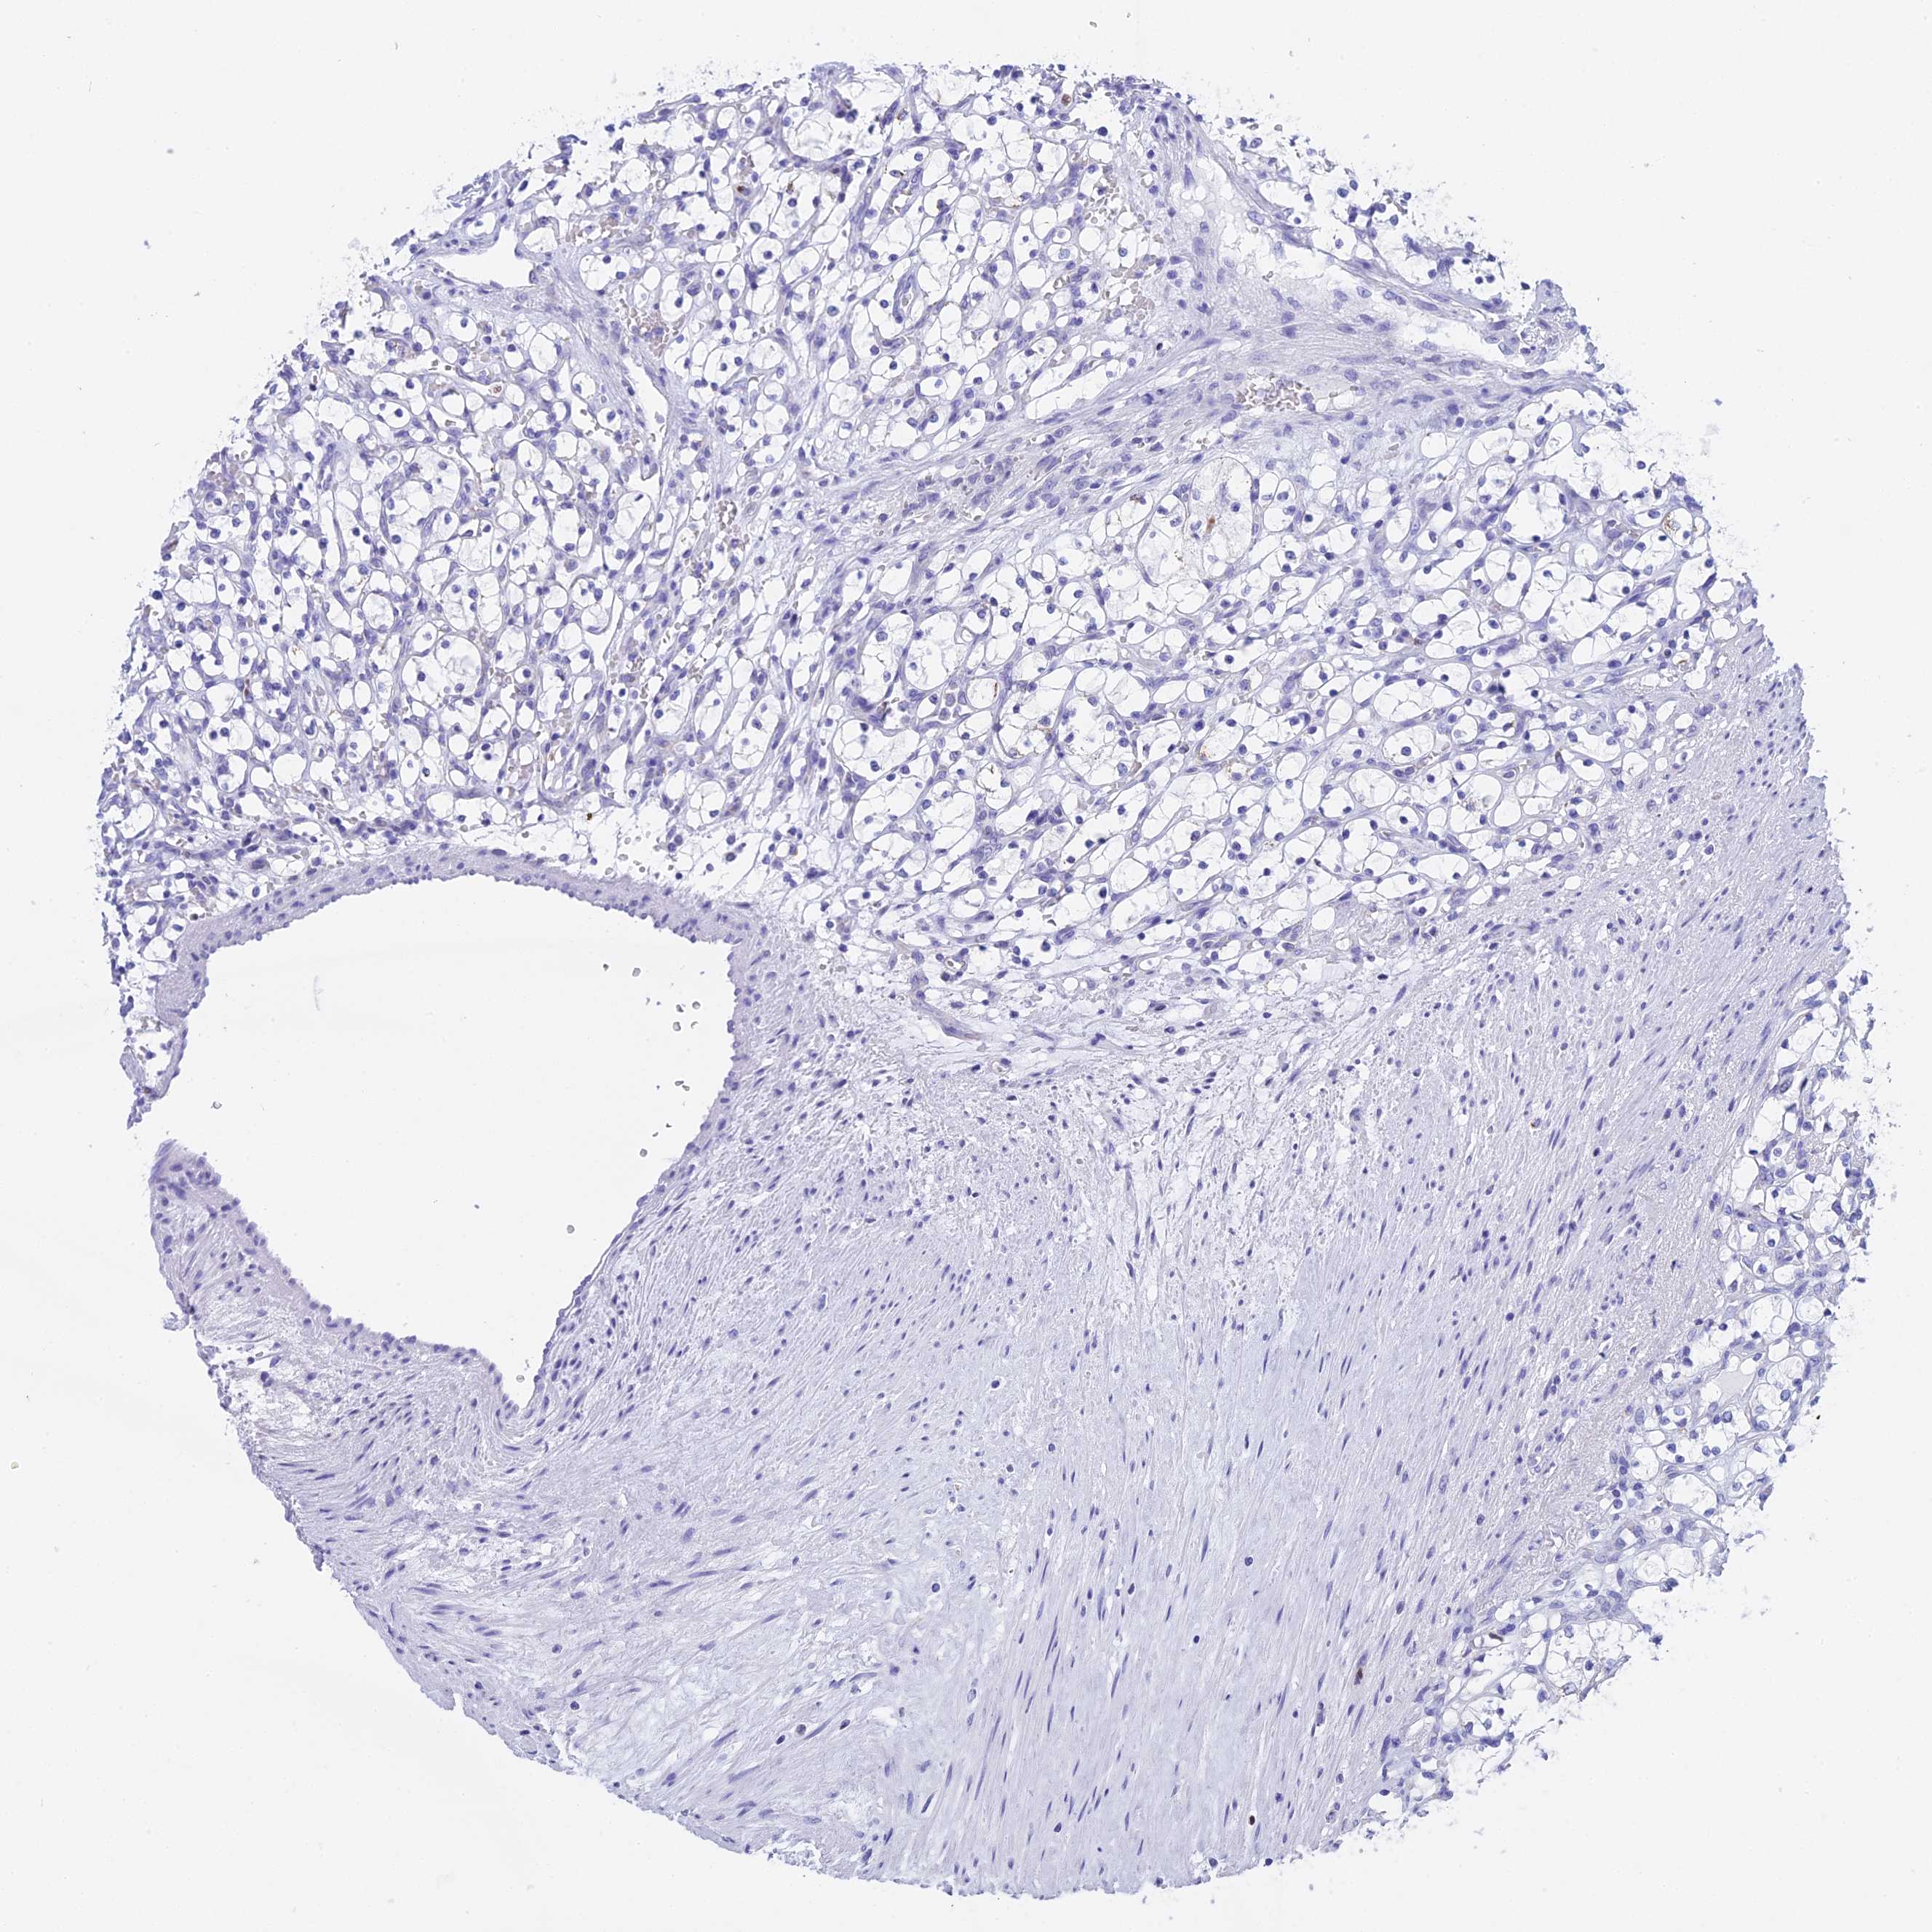

CANCER RENAL CANCER Show tissue menu

KICH TCGA KIRC TCGA KIRC VALIDATION KIRP TCGA PROTEIN RCC CPTAC PROTEIN EXPRESSION

ANTIBODIES

AND

VALIDATION